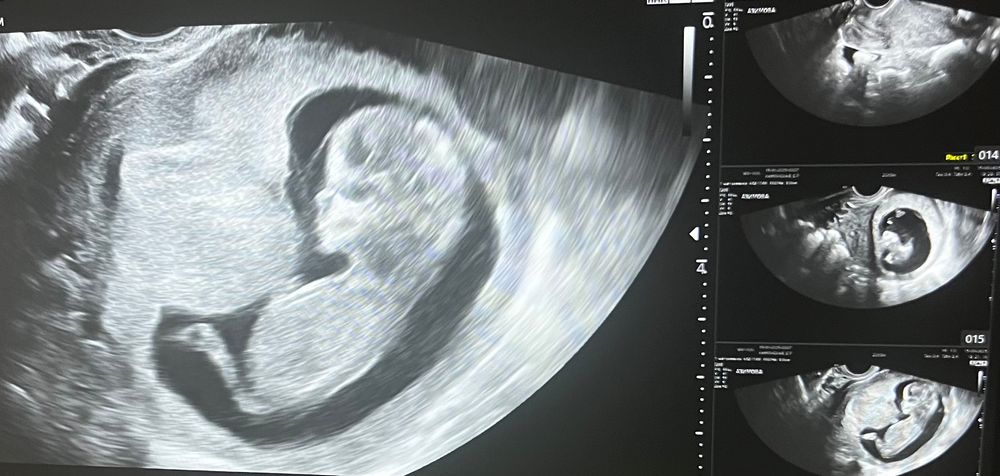

Alexandra Frolova в Клуб беременных год мальчик или девочка? Пол малыша срок 13 недель первый скрининг может кто разглядит 😅 Посмотрите еще 20 записей на эту тему Лучший ответ Диана Ли Девочка 13.01.2025 Ответить Отменить Ответить Светлана Тоже вижу принцессу ☺️ 13.01.2025 Ответить Анастасия Поделюсь для сравнения, на узи 12 недель, мальчик 13.01.2025 Ответить Оля☀️ Девочка) но это вообще ничем не подкреплено))) 13.01.2025 Ответить Первый скрининг и пол малыша У нас будет еще один мальчик! Чаты Беременных Выберите чат: Январята-2026 Февралята-2026 Мартята-2026 Апрелята-2026 Майчата-2026 Июнята-2026 Июлята-2026 Августята-2026